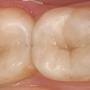

anicenne obturation en composite

fraisage léger de la dent

le nouveau composite en place